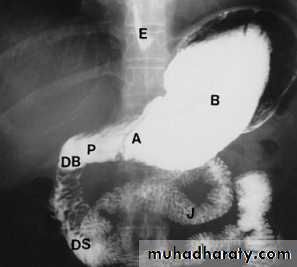

Barium meal examination (the patient instruct to fast at least 6 hours then drinks about 200 cc of barium) is now rarely performed.Upper GI endoscopy is widely used as the initial investigation in patients with possible disease of the stomach and duodenum. It enables the mucosa of the stomach and duodenum to be directly inspected and biopsied.

Normal appearance of the small bowel

The normal SB occupies the central lower abdomen.

The terminal ileum enters the medial aspect of the cecum through the ileocecal valve.

Normal mucosa exhibit a feathery appearance.

The diameter of SB loop should not exceeds 3 cm .